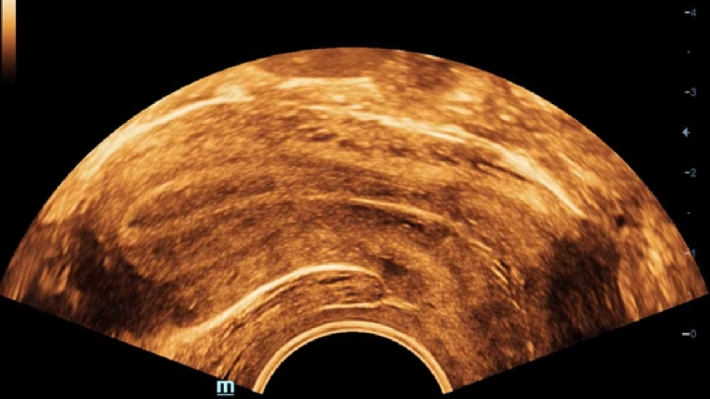

УЗИ-аппарат Mindray DC-70 — это современная ультразвуковая система экспертного класса, предназначенная для проведения диагностических исследований в различных областях медицины, включая кардиологию, акушерство и гинекологию, абдоминальные и сосудистые исследования. Аппарат сочетает высокое качество изображения с широким набором функциональных возможностей, что делает его эффективным инструментом для диагностики.

• Многофункциональность: Поддержка различных режимов сканирования, включая 2D, 3D/4D, цветное допплеровское картирование и другие, позволяет использовать аппарат для широкого спектра медицинских задач;

• V11-3E — микроконвексный внутриполостной датчик;

• V11-3BE — микроконвексный внутриполостной датчик с изогнутой рукояткой;

• CB10-4E — эндоректальный биплановый датчик;

Изображения